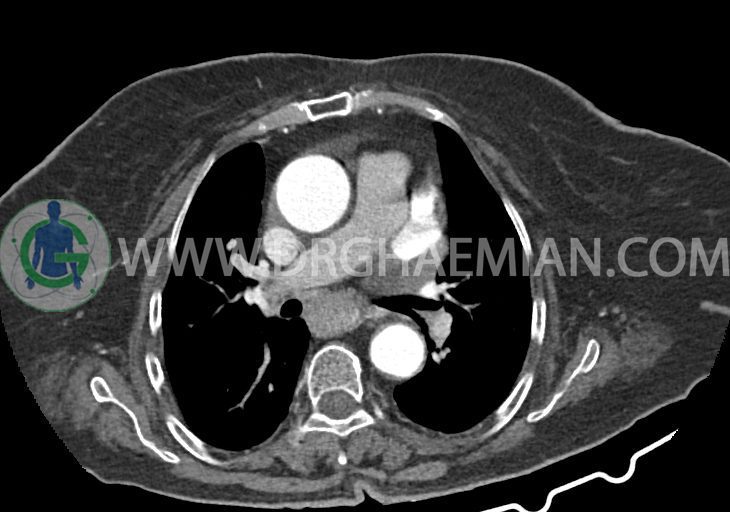

تراشه و برونش های اصلی نرمال اند. پنومونی، پلورال افیوژن، جابجایی محتویات مدیاستن ، فیبروز ریوی و Collection مشهود نیست.

–یک ندول به ابعاد 19x18mm با حدود اسپیلوکه در سگمان لترال RML و دو ندول کوچکتر در مجاورت فوقانی آن به اقطار 6mm و 5mm ( مطرح کننده کارسینوم برونکوژنیک یا متاستاز )

–ندول کلسیفیه به قطر 6mm در لوب چپ تیروئید (نیازمند تطابق سونولوژیک)